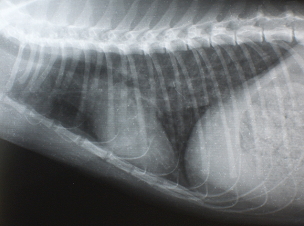

X線検査

気管支パターンが認められます。また横隔膜が斜めになり、暗い肺野の部分が多くなります。時に右の中葉や左の後葉に硬化像が認められます。

| Figure 2. 治療前のX線写真、肺のX線の透過性の亢進と気管支の肥厚を認める | Figure 3. 治療3日後のX線写真、肺の透過性が低下(改善している)している。 |